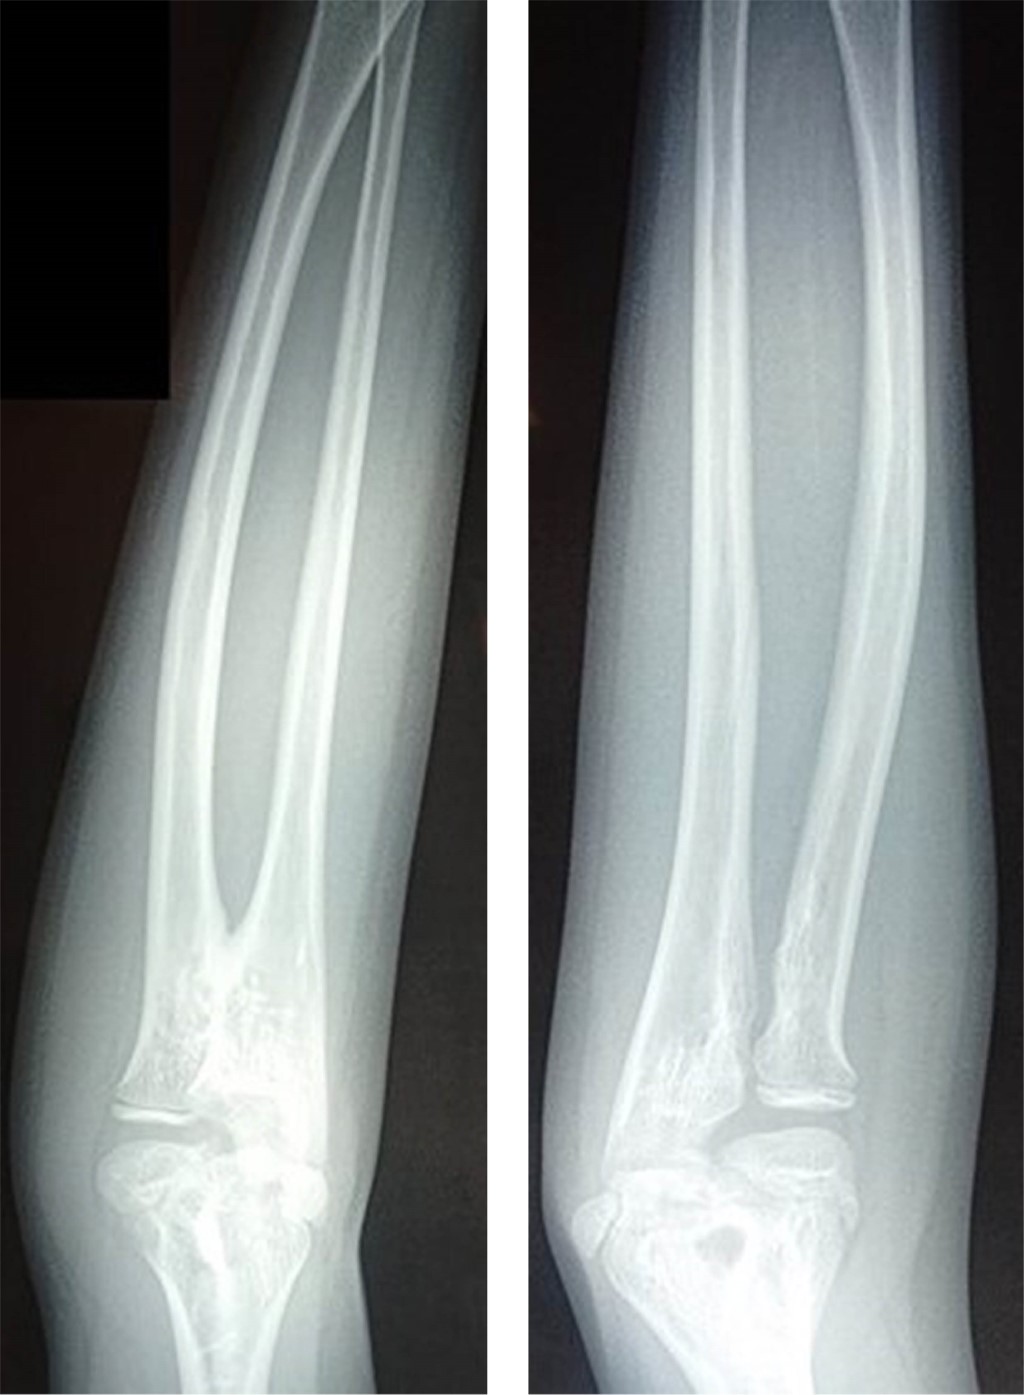

Por las características del cuadro clínico, se decide tomar radiografías radiocubital bilateral (Figura 2). Con los hallazgos radiográficos se llega al diagnóstico de sinostosis radiocubital proximal congénita unilateral, solicitando interconsulta al servicio de traumatología y ortopedia pediátrica. Se decide no brindar tratamiento, y solamente mantener vigilancia por consulta externa.

Figura 2